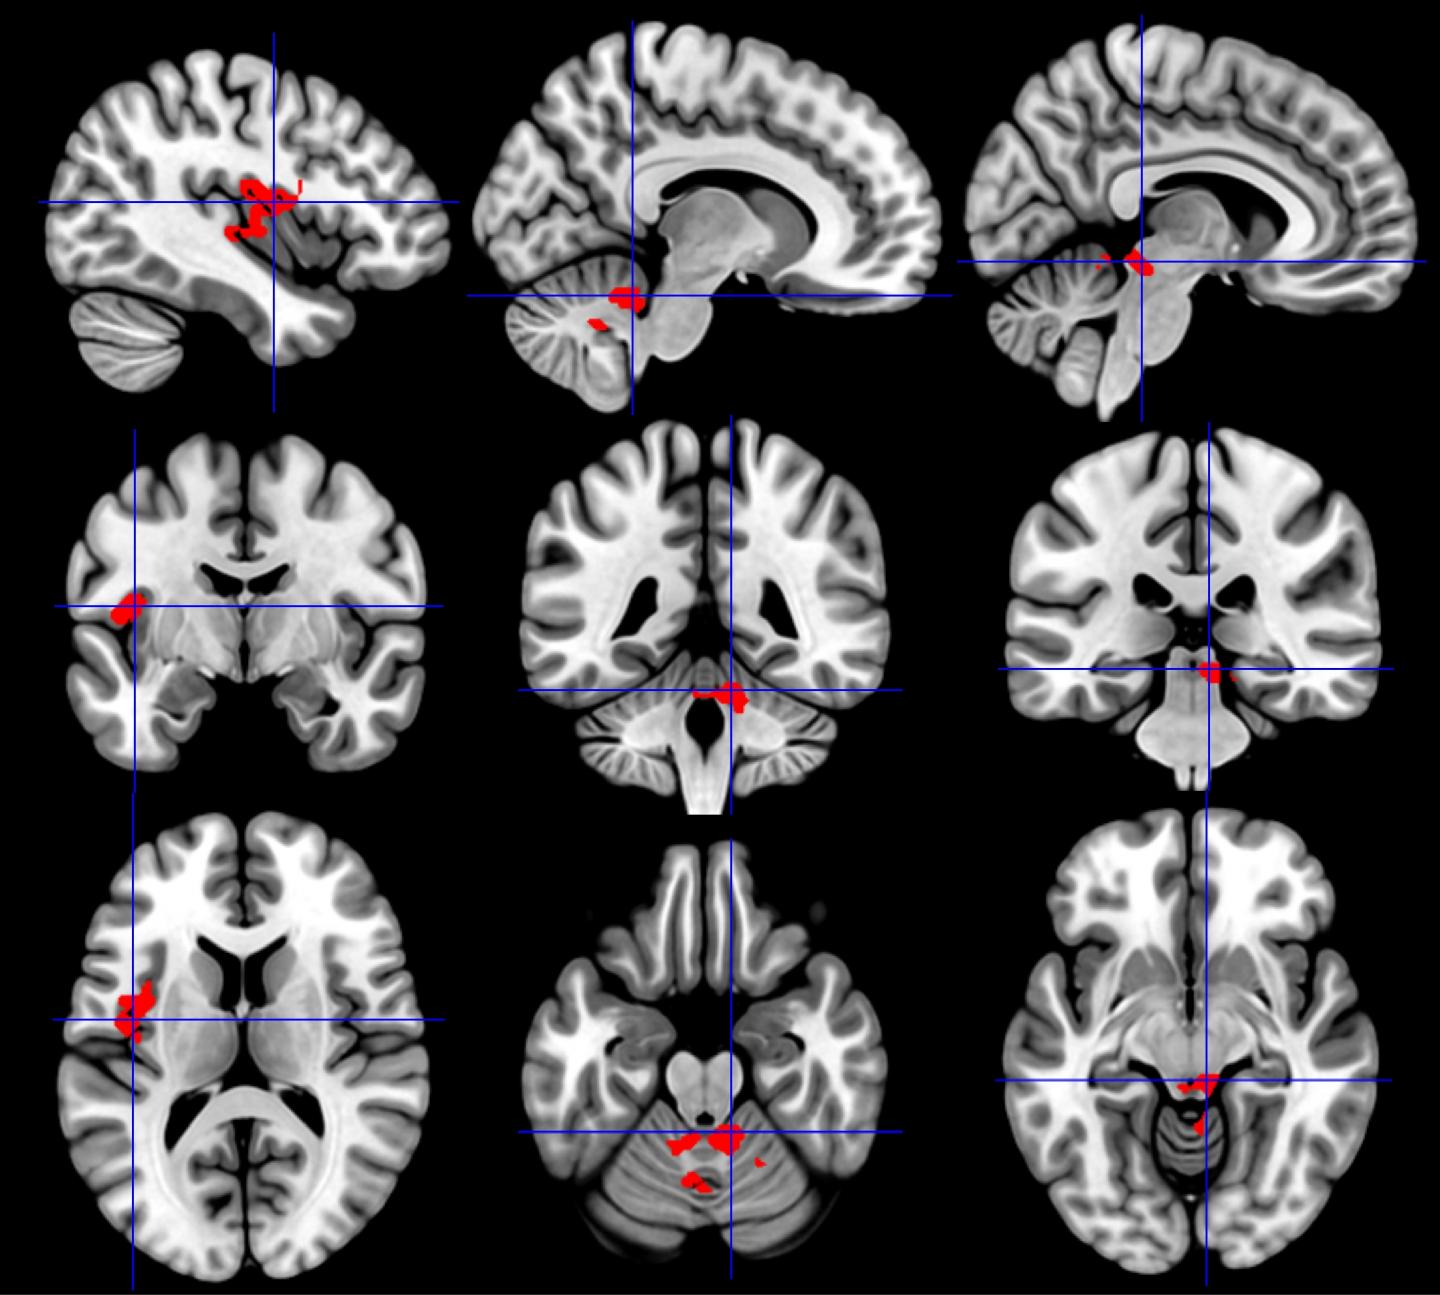

Both GWI and CFS share common features: cognitive dysfunction, pain and fatigue primarily following physical exercise. To determine how these conditions affect brain function, investigators studied neuronal activation using functional MRI (fMRI) during a cognitive task a day before and a day after bicycle exercise stress tests in their different groups: 38 CFS patients, 80 GWI patients, and a control group of 23 healthy sedentary volunteers. Brain activation during a working memory task was compared between the pre- and post-exercise fMRI studies, and between CFS and GWI groups.

Before exercise, brain activation was similar between groups. However, after exercise the CFS group showed significantly increased activation of the midbrain, while GWI had the opposite effect, with decreased activation in this vital region of the arousal network. CFS also had increased activation in the insula. In contrast, GWI, but not CFS, had a decrease in activation of the cerebellum after exercise. The findings show that specific brain regions acted in opposing ways, representing a differentiation between GWI and CFS.

While these areas are involved in pain perception, among their many other tasks, "this doesn't mean more or less activity is directly related to pain," says Washington. "What it does show is that the two conditions are distinct from each other and involve different cellular/molecular mechanisms."

The second study, led by Pepermintwala, looked more closely at specific regions within the brain stem and confirmed that CFS had significantly increased activation during the cognitive task after the exercise provocations, while GWI had significantly reduced activation.